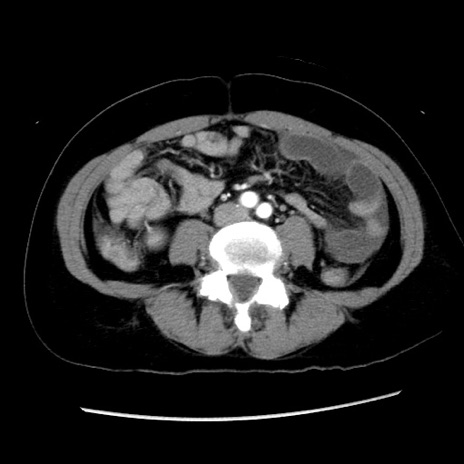

症例10(横断像)

【症例】 50歳代女性

【主訴】 腹痛

【現病歴】前日生レバーを食べた。今朝に排便あり。 昼前に突然発症の腹痛を生じ、当院救急外来を受診した。

【既往歴】 子宮筋腫にてで子宮全摘後

【身体所見】 意識清明、腹部:平坦、軟、下腹部やや左を中心に圧痛・反跳痛あり、筋性防御あり

【データ】WBC 7800、CRP 0.07